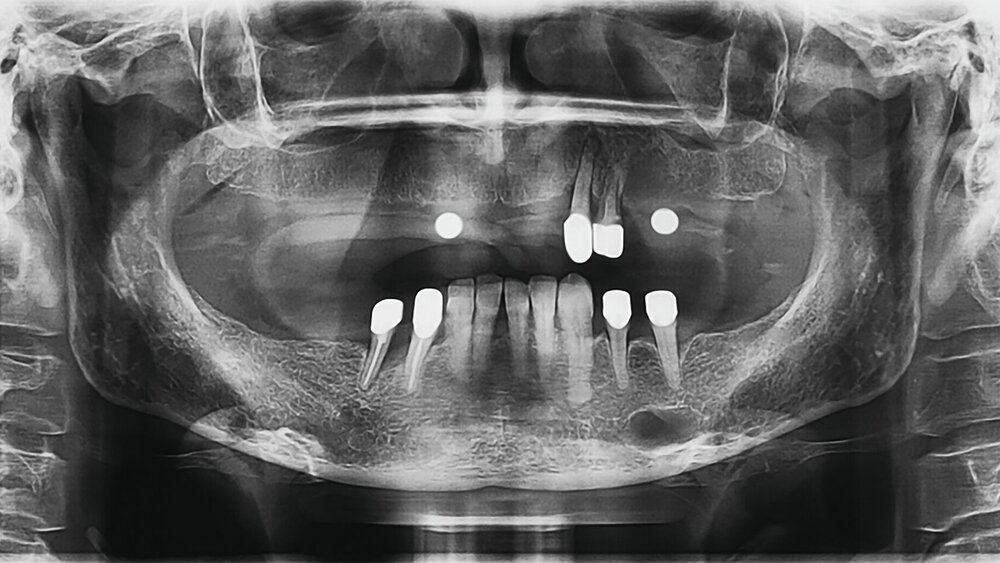

Die Patientin zeigte keine Hypästhesien in den Bereichen der Nervenaustrittspunkte. Die Zähne 42 bis 35 waren vital. Die Zähne 23, 24 und 44 sollten präimplantologisch extrahiert werden. Im Zuge der Implantatplanung wurde eine Panoramaschichtaufnahme (PSA) mit Messkugeln angefertigt (Abbildung 1).

In der PSA zeigte sich als Zufallsbefund im Bereich des Foramen mentale linksseitig eine etwa 12 mm x 8 mm große, hypodense, scharf begrenzte Raumforderung ohne erkennbare Korrelationzu den Zähnen 33, 34 und 35. Zur weiteren Diagnostik und Beurteilung der Ausdehnung der Raumforderung wurde eine erweiterte Bildgebung im Sinne einer digitalen Volumentomografie (DVT) erstellt (Abbildung 2).

Die DVT bestätigte den Befund in der PSA. Die dreidimensionale digitale Darstellung zeigte einen Verlauf des Nervus alveolaris inferior links durch die fragliche Osteolyse. Auf einer vor zehn Jahren alio loco angefertigten PSA war der suspekte Befund auch schon sichtbar gewesen, jedoch mit deutlich geringerem Volumen.